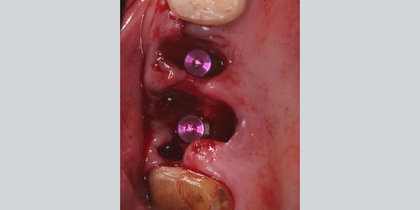

• Glidewell HT Implants are immediately placed into extraction sites in the areas of tooth #3 & #4. thumbnail image

Extraction with Immediate Placement

Glidewell HT Implants are immediately placed into extraction sites in the areas of tooth #3 & #4.